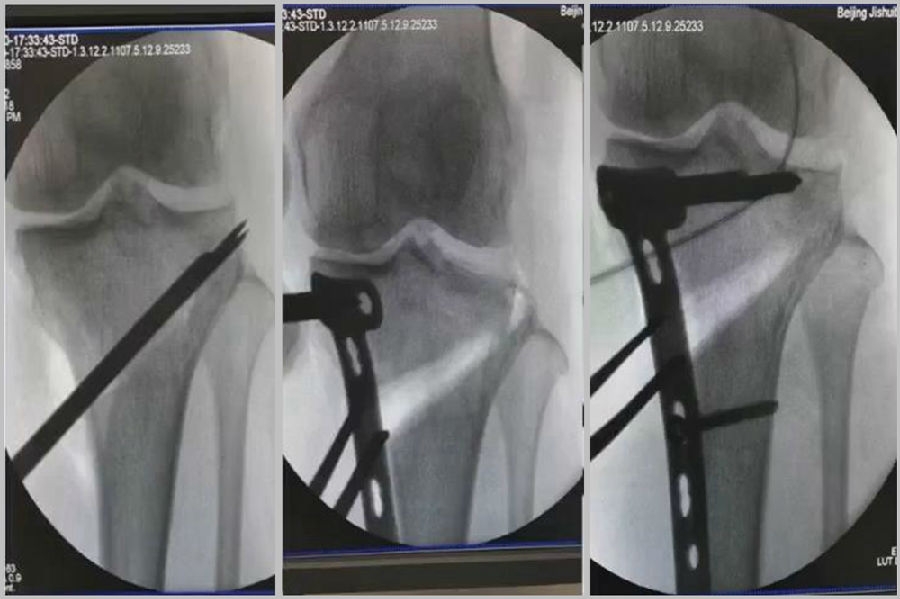

(2)Ⅱ型骨折

当出现Ⅱ型骨折时要特别注意,因为此时截骨的远端就是骨折的远端,近端只有上胫腓周围骨筋膜存在,所以相对来说Ⅱ型骨折并不稳定。

首先用拉力螺钉复位,调整好力线。然后做结构性植骨,延迟负重,所谓延迟负重就是延迟到外侧合页和上行截骨线处达到初始愈合,然后再让患者进行负重。如果不做结构植骨加延迟负重,就会出现一些非常严重的现象,如不愈合。

拉力钉复位,结构性植骨

左侧患者未植骨正常负重,术后4个月不愈合;右侧患者非结构性植骨过早负重,术后1年未愈合